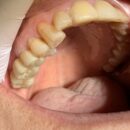

2025.11.22 下顎両側456のインプラントハイブリッド…… 下顎両側456のインプラントハイブリッドの上部構造 クリアランスが無くバイト調整に苦心しました。対合歯は弊社製作のジルコニアフルマウスです。……